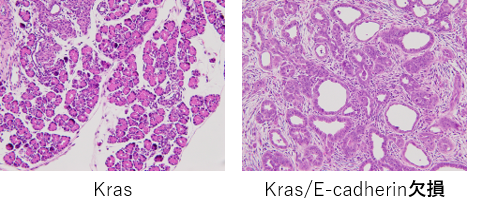

生後5日目のKras及びKras/E-cadherin欠損マウスの病理像。E-cadherin欠損ではすでに腫瘍性変化が起きている。

膵臓特異的にE-cadherinを欠損させると、膵腺房細胞は崩壊し、膵炎様の所見を呈する。一方、KRas変異の存在下では前癌病変であるPanINを速やかに形成する。

まず膵特異的E-cadherinのノックアウトマウスを作製したところ、全て生後28日以内に死亡しました。出生時の膵実質の形態に正常マウスとの違いは見られませんでしたが、生後6日目以降では、腺房導管異形成、アポトーシスの亢進、炎症細胞浸潤および線維化の亢進を認め、膵炎様の組織像を呈していました。次に、腫瘍発生との関連を解析するため、上記ノックアウトマウスと活性型Krasマウス(KrasG12D)を掛け合わせたところ、生後8日目の時点で瀕死状態となり、広範な間質反応を伴う異型腺管が認められ、膵癌に類似した組織像を呈しました。